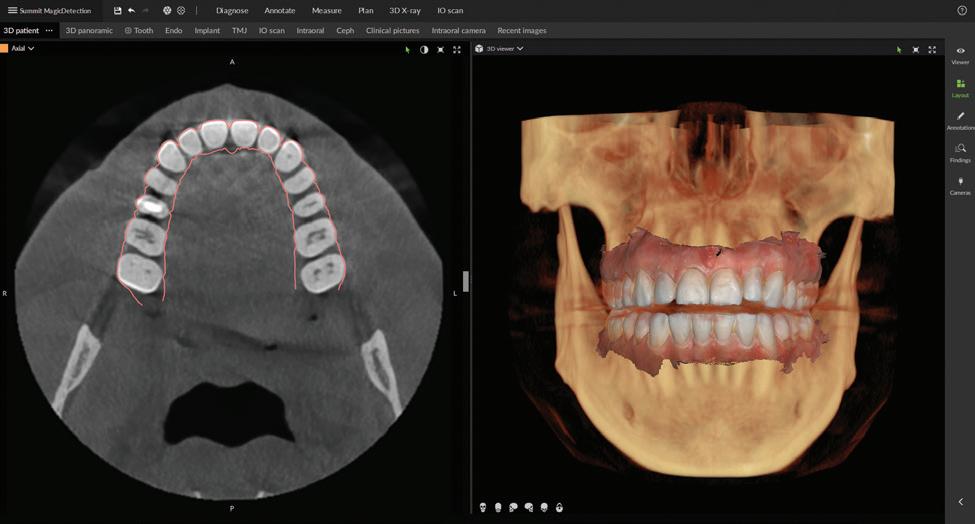

Seamless integration with new DTX Studio™ Clinic software

P acked with AI-assisted software features, DTX Studio™ Clinic complements OP 3D LX in numerous ways—for example, correcting patient positioning errors and detecting

landmarks, annotating mandibular nerve canals, tracing patientspecific panoramic curves for mandible and maxilla and merging CBCT and intraoral scan data for improved implant planning. These intuitive award-winning software features support a more efficient workflow allowing you to spend less time in the software and more time with your patient.